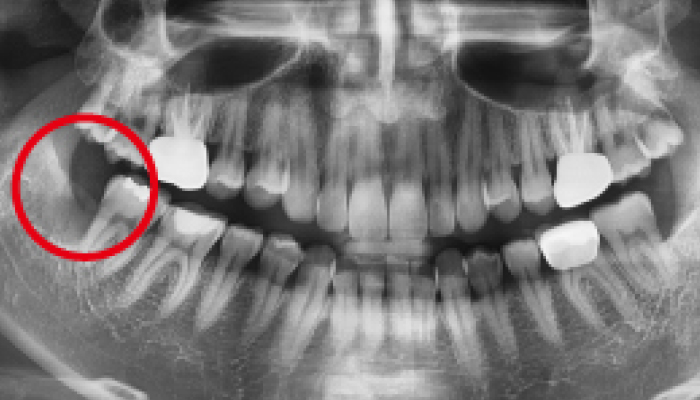

매복 사랑니 발치

이OO님 전후사진 / 치료 기간 : 30분 / 당일 사랑니 발치

매복 사랑니 발치

이OO님 전후사진 / 치료 기간 : 30분 / 당일 사랑니 발치

-

Before

로그인 후 이용해주세요

After

매복 사랑니 발치

심OO님 전후사진 / 치료 기간 : 30분 / 당일 사랑니 발치

-

Before

로그인 후 이용해주세요

After

매복 사랑니 발치

서OO님 전후사진 / 치료 기간 : 30분 / 당일 사랑니 발치

-

Before

로그인 후 이용해주세요

After

매복 사랑니 발치

김OO님 전후사진 / 치료 기간 : 30분 / 당일 사랑니 발치

-

Before

로그인 후 이용해주세요

After

당일 사랑니 발치

이OO님 전후사진 / 치료 기간 : 30분 / 당일 사랑니 발치

-

Before

로그인 후 이용해주세요

After

매복 사랑니 발치

노OO님 전후사진 / 치료 기간 : 30분 / 당일 사랑니 발치